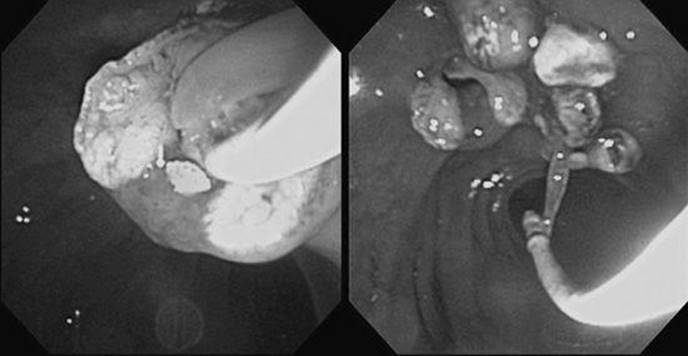

A 42-year-old man with no previous health problems presented to the hospital with a 2-day history of severe intermittent epigastric pain radiating to his back with associated nausea and vomiting. He denied alcohol abuse, prior pancreatitis, or gallstones. He had lost about 35 pounds over the last 4 months and attributed the weight loss to intentional dieting and exercise. On examination, he was febrile, jaundiced, and tender to palpation over the epigastrium. Laboratory testing revealed a leukocyte count of 19,000 with a left shift, alkaline phosphatase of 650 IU/L, bilirubin of 4.8 mg/dL, and amylase of 2500 IU/L. An abdominal ultrasound showed some “sludge” in the gallbladder but was otherwise normal. What is the most appropriate therapy for this patient?

Figure 39-3 See also color plate.

Early administration of intravenous (IV) antibiotics, IV fluids, and other supportive intensive care measures are important. Endoscopic retrograde cholangiography (ERC) with sphincterotomy and stone extraction (see Figure 39-3) are also indicated in the setting of acute gallstone-related cholangitis and severe pancreatitis.

What is the approach to a patient with acute bacterial cholangitis due to an obstructed bile duct?

Initial therapy should include blood cultures with empiric use of intravenous antibiotics. About 85%–90% of patients have a response to initial antibiotic and supportive therapy before biliary interventions. Biliary drainage is mandatory. Its urgency is dictated by the response to antibiotics and supportive care. ERCP with stent, nasobiliary drain or sphincterotomy, and duct drainage is associated with significantly lower morbidity and mortality compared to surgery. If endoscopic approaches fail, then surgical or percutaneous approaches should be tried.